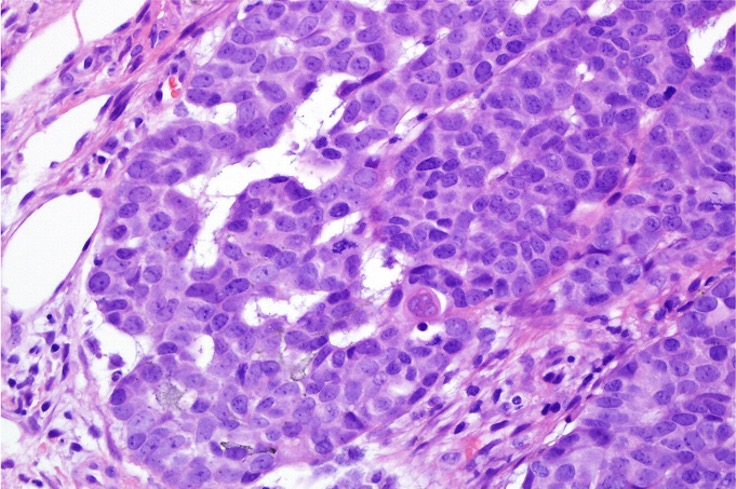

Histological features

•Usually well circumscribed

•Nodular or multinodular

•Basaloid population with prominent nucleoli accompanied by supramatricial and ghost cells

•Variable pleomorphism

•Mitoses may be conspicuous

•Heavily pigmented dendritic +/- epithelioid melanocytes